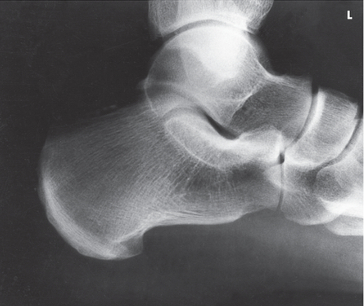

Name this projection.

Lateral ankle

What type of projection is it?

Mediolateral

Which side is the patient turned toward?

Affected side

Where does the CR enter?

Perpendicular to the ankle joint, entering at the medial malleolus

How do you evaluate for a true lateral?

The tibiotalar joint will be well visualized, and the fibula will be over the posterior half of the tibia

How much of the distal tibia and fibula must be included?

1/3

Which joint is well visualized?

Tibiotalar